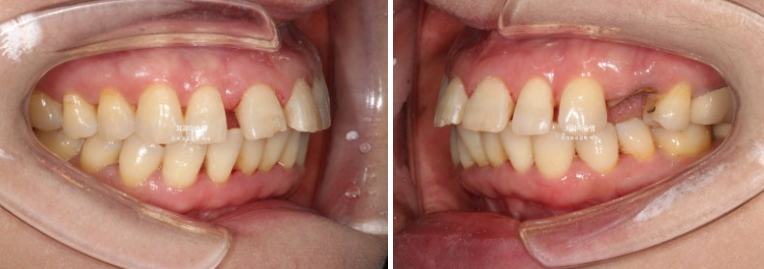

24년 7월 50대 환자분께서 교정치료를 위해 오셨습니다.

앞니가 세로 길이보다 가로길이가 더 긴, 한마디로 납작한 형태입니다.

치아 사이사이 벌어진 틈을 레진으로 메꿔놓고 지내온 것입니다.

충치로 인해 어금니들을 발치하게 되면서 교정치료를 병행하고자 오셨습니다.

일단 앞니 사이사이 레진을 제거해 보았습니다.

아래 앞니 사이 치석도 같이 제거합니다.